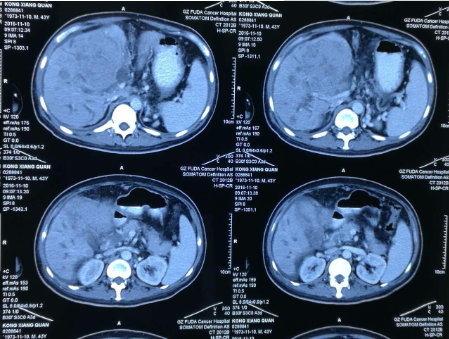

孔祥泉,男性,43岁,因皮肤发黄、肝区不适一个月,各种检查结果很不乐观。MR检查见:“S4/8肝内多发结节及团块(最大102mm*81mm),考虑肝癌合并子灶,侵犯肝门区胆管,门静脉主干及分支、肝右静脉受压、管腔变窄,肝内胆管扩张。胆囊增大并壁周水肿。肝硬化、脾大、少量腹水,食管下段、胃底及脾周静脉曲张,肝门区、门腔间隙及腹主动脉旁淋巴结(百度搜索:广州复大肿瘤医院)。

山东肿瘤医院认准广州复大医院:重症晚期肝癌患者恢复健康